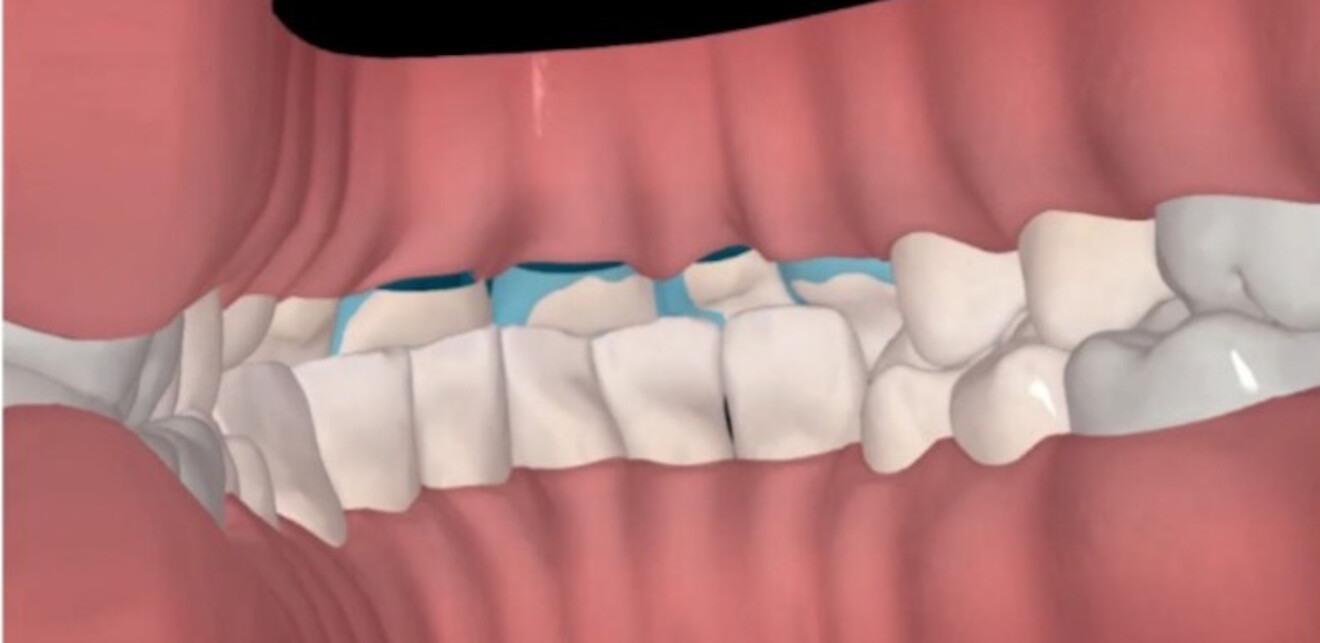

Figs. 1a & b: Side-by-side cross-sectional analysis of the initial (a) and post-restorative treatment position (b), highlighting vertical space creation with orthodontic treatment.

An approach involving only restorative dentistry was considered; however, owing to the heavy incisal intercuspation as a result of acid erosion, wear and overeruption, either significant further reduction of the maxillary and mandibular tooth structure or increase of the vertical dimension of occlusion through full mouth-rehabilitation would have been required. An alternative option of a short course (14 weeks) of Invisalign treatment was discussed as a means of maximising vertical, interproximal and inter-arch space while maintaining the stable, functional posterior occlusion and vertical dimension of occlusion.

The importance of aligner compliance was stressed, and the patient progressed well with treatment, which included take-home whitening along with the aligner therapy. Analysis of the situation after aligner therapy was performed, including review with exocad software (Figs. 2–5). This was followed by the placement of anterior resin composite restorations (IPS Empress Direct, Bleach-L Dentin; Ivoclar). No preparation or reduction of the remaining dentition was performed—instead, space was created via preparation with plastic.